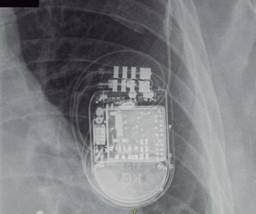

Both procedures were carried out uneventfully, and the patient was discharged the next day. One week after the procedure, the patient presented with a device pocket hematoma which developed after initiation of rivaroxaban 20 mg P.O.; transient suspension of his anticoagulant treatment and physical measures (ice packs and compression) were sufficient to achieve hematoma resolution. Adequate device function was confirmed with significant improvement of his heart failure symptoms. During his second follow up visit six months after device implant, loss of capture of the left ventricular (LV) lead was seen. Chest X ray (Figure 1) revealed a slightly pulled right ventricular electrode and a missing LV lead. Detailed image review (Figure 2) revealed the LV lead located behind the device generator, compatible with lead dislodgement due to «reel» syndrome. The patient underwent LV lead repositioning, during which a large device pocket was found and pocket remodeling (using absorbable sutures) was undertaken. During follow up, no further events of lead dislodgement have been found.

Figure 1: Chest X-ray of the patient. The device is in a left subcutaneous pocket, with two leads connected, but only one within the vascular space. An empty fixation sleeve is seen. The right ventricular lead is slightly pulled. The round radio-opaque images are pellets from a gunshot wound the patient suffered several years earlier.